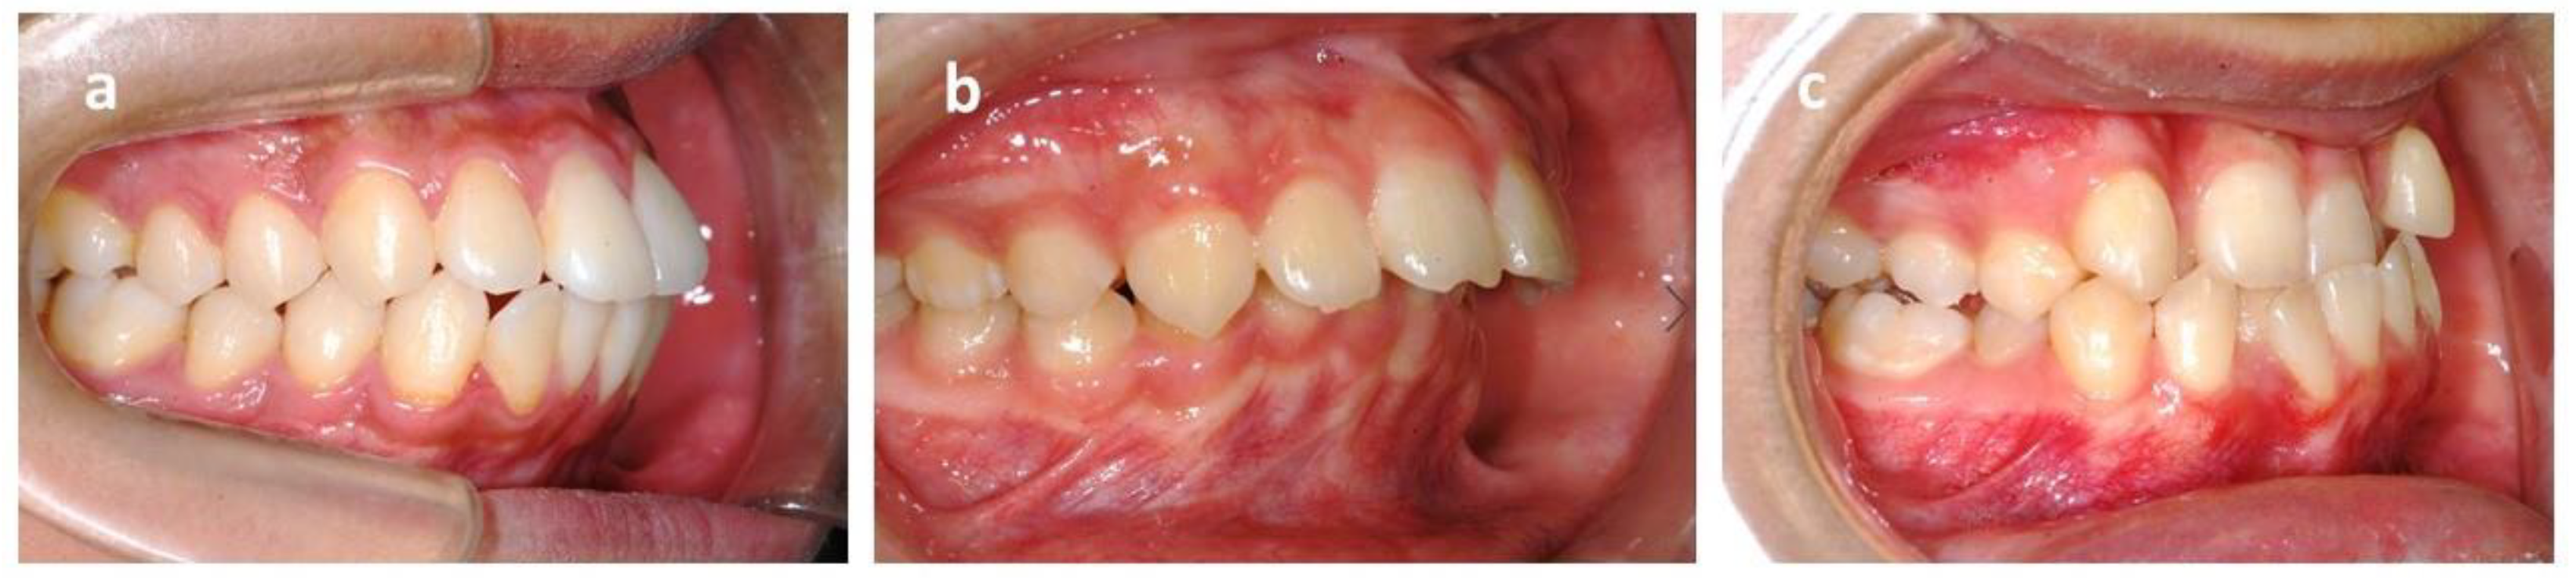

The skeletal relationship between the maxilla and mandible of orthodontic patients was categorized as Class I, Class II, or Class III [35,36,37,38] (Figure 1 and Figure 2). Steiner’s analysis [39] and Tweed analysis [40] were used for the measurements according to the analysis of St. Louis University in the United States, where the first author was trained for her orthodontic graduate program. The dental relationship between the maxilla and mandible of orthodontic patients was defined as molar Class I, Class II, or Class III (Figure 3). The DMFS index was expressed as the total number of teeth that were decayed (D), missing (M), or filled (F) in an individual with permanent dentition. There were five surfaces (facial, lingual, mesial, distal, and occlusal) for the posterior teeth and four surfaces (facial, lingual, mesial, and distal) for the anterior teeth when the DMFS index was calculated.

Figure 2. Sagittal skeletal classification based on ANB angle. ANB: The angle is constructed by connecting the A point, nasion, and B point. According to the Steiner analysis, the measurement represents the skeletal relationship between the maxilla and mandible. (a) Class I relationship: ANB is between 2 and 4. (b) Class II relationship: ANB is greater than 4. (c) Class III relationship: ANB is below 2 or negative.